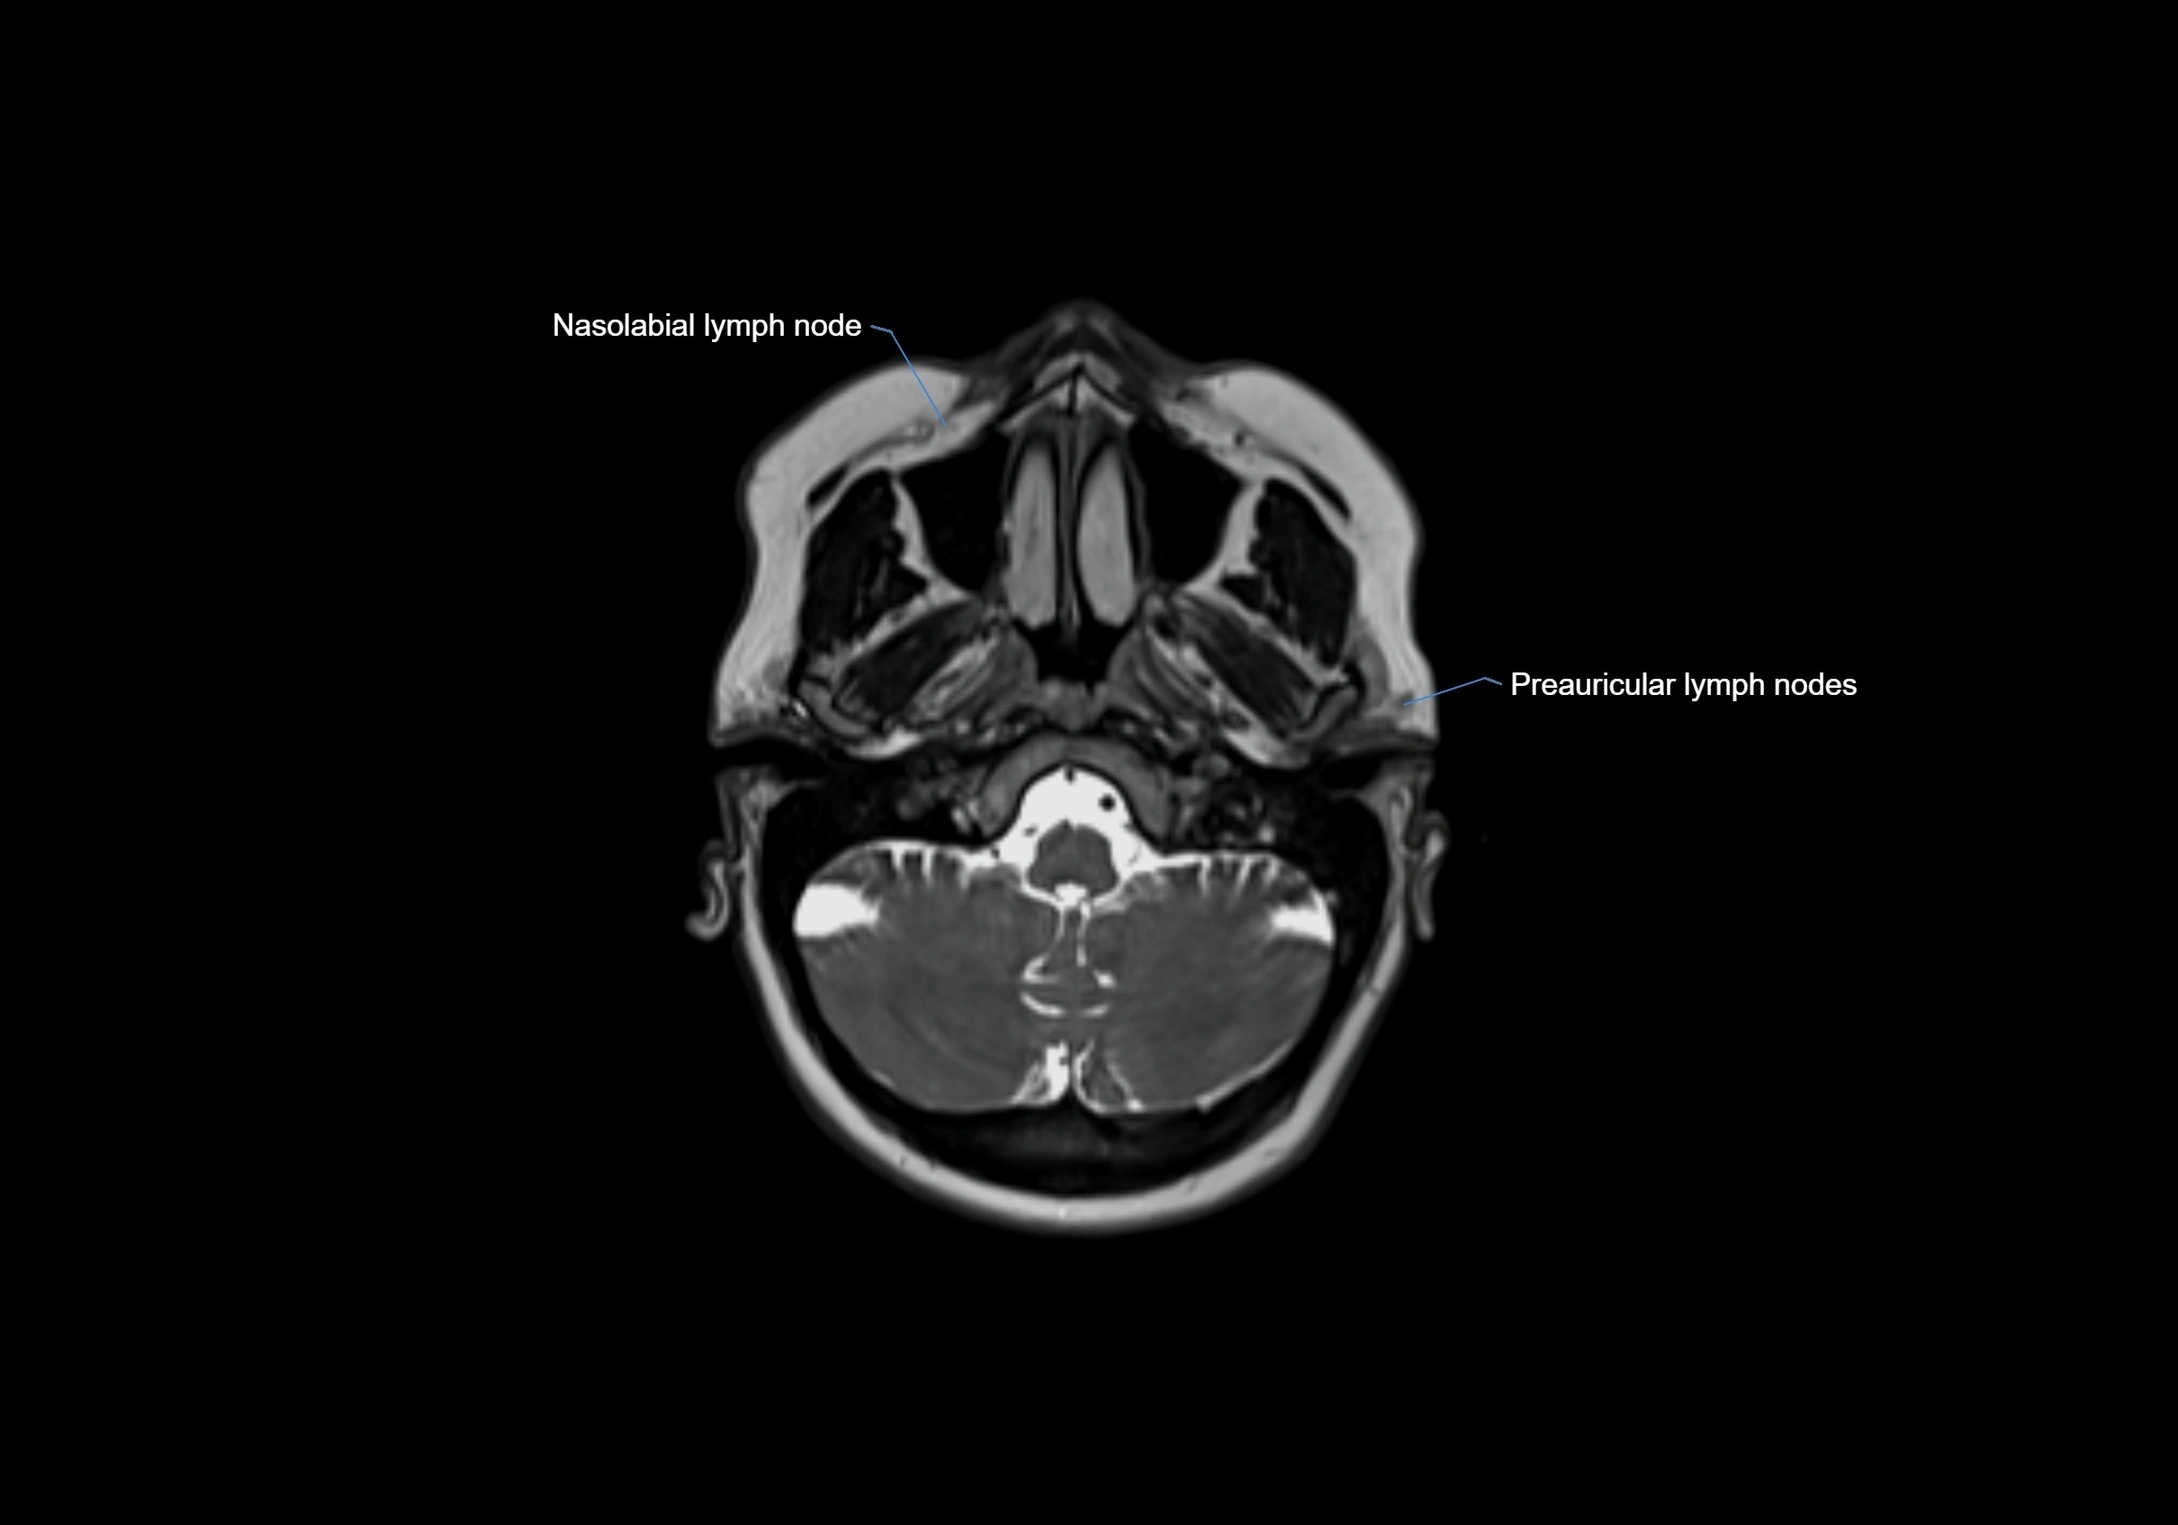

Accessory lymph nodes are small, secondary lymph nodes located along the main facial and cervical lymphatic chains, often adjacent to primary lymph nodes, such as preauricular, submandibular, or occipital nodes. They are typically less than 5 mm in diameter, embedded within subcutaneous fat or connective tissue, and may be variable in number and location. These nodes provide additional filtration and immune surveillance for lymph collected from the face, scalp, and neck regions. Accessory lymph nodes are usually non-palpable in healthy individuals but may enlarge in response to infection, inflammation, or metastasis, making them clinically significant.

Location

• Found along primary lymph node chains, including preauricular, submandibular, parotid, and occipital regions

MRI Appearance

T2-weighted images:

• Nodes show intermediate signal, with surrounding fat bright

• Useful for detecting edema, inflammation, or infiltration

• Fatty hilum may appear slightly hyperintense relative to cortex